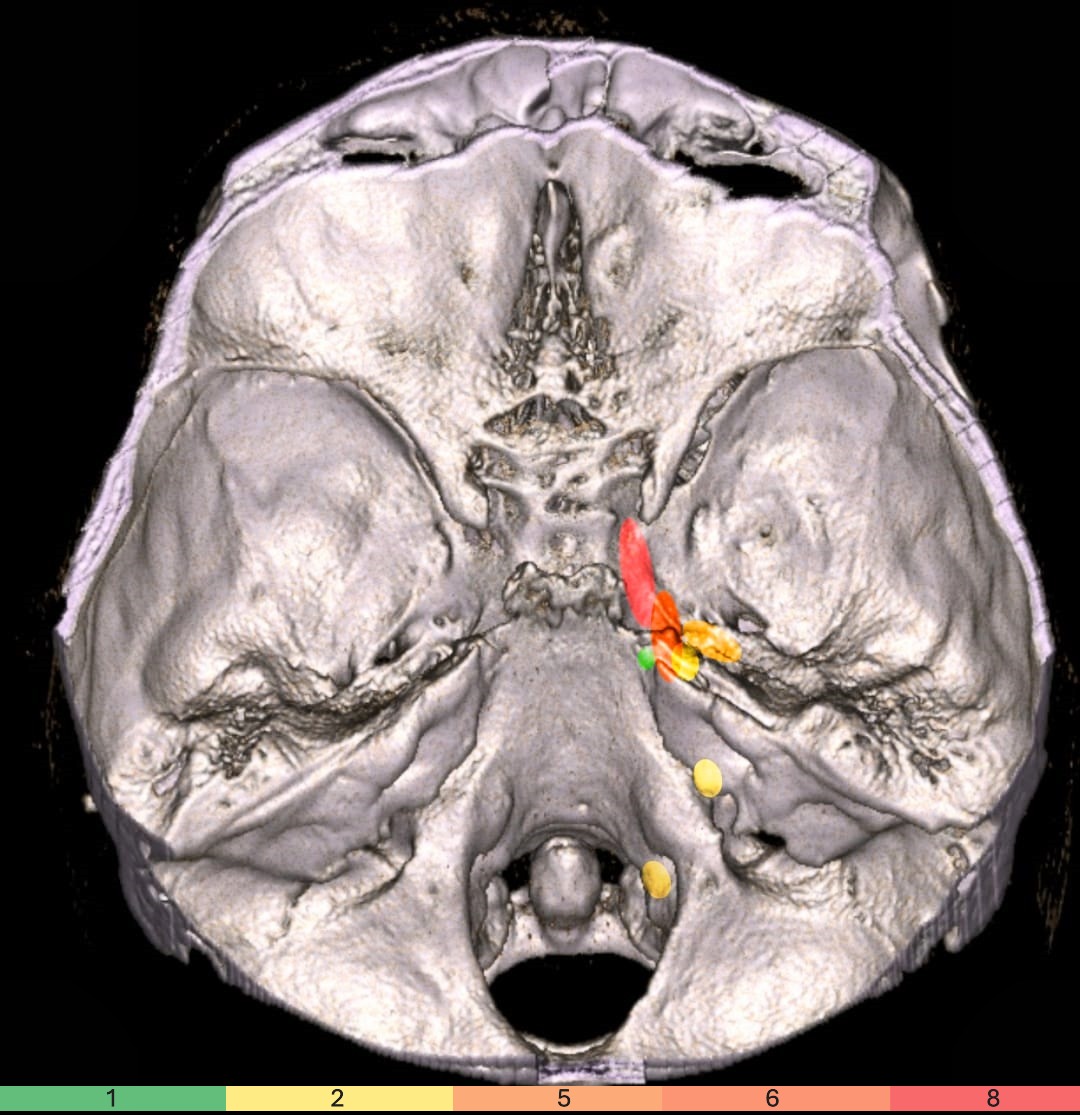

Transcranial doppler for risk assessment of subarachnoid hemorrhage

Screenshot 2025 06 02 at 1.53.45 pm

Screenshot 2025 06 02 at 1.54.04 pm

Screenshot 2025 06 02 at 1.54.22 pm